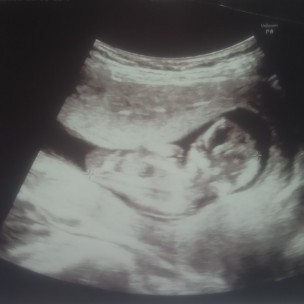

3เดือนค่ะ